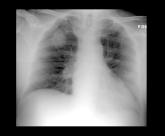

Patients treated with intravenous spesolimab showed significant clearance, but also susceptibility to infections.